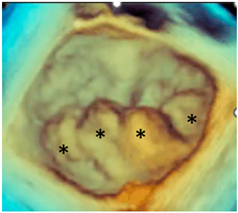

| Forme fruste | In this phenotype, the entire posterior leaflet is redundant and is affected by myxomatous degeneration, while the anterior leaflet is macroscopically and histologically normal. It can be speculated that this phenotype is an incomplete form of Barlow’s disease. The figure shows multiple prolapses (asterisks) of the posterior leaflet. |  |